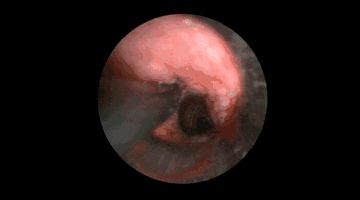

低温等离子术消融治疗

治疗前:管腔狭窄约80% 治疗后:狭窄约10%